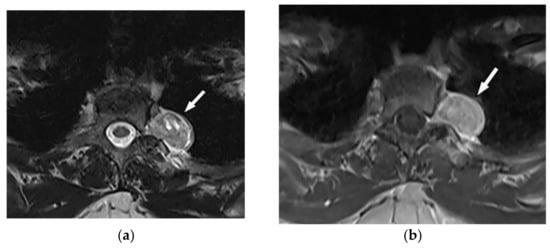

9.1.1. Schwannoma

Schwannoma is an encapsulated slow-growing peripheral nerve sheet neoplasm typically occurring in patients between 20–50 years old [6,16]. Chest wall schwannomas arise from spinal nerve roots with a dumbbell shape appearance and extend through the course of intercostal nerves, paravertebral region, or spinal canal [7,43].

Schwannoma presents a well-defined homogenous mass on CT scan with attenuation similar or less than muscle. The “Fat-split” sign caused by adjacent surrounding fat is indicative of its non-infiltrating growing pattern. It also shows remarkable post-contrast enhancement except for areas of necrosis or cystic changes (Figure 14). On MR images, it has intensity equal to or slightly more than muscle on T1-weighted and marked hyperintensity on T2-weighted images. Scalloping or bony erosions might be the only radiographic manifestations reflecting its benign nature [6,7,16,43].

Figure 14.

A 39-year-old woman with right vague chest pain. The contrast-enhanced axial CT demonstrates right-sided well-defined posterior mediastinal paraspinal mass with foci of calcifications within it. The round configuration is typical for peripheral nerve tumors. The attenuation is equal to chest wall muscles. Histopathological examination confirms Schwannoma.

9.1.2. Neurofibroma

Neurofibroma is another slow-growing peripheral nerve sheet neoplasm that affects patients in their 20s to 30s with equal male and female prevalence. Localized Neurofibroma, which includes approximately 90% of cases, is not typically associated with neurofibromatosis type 1 (NF1). However, the majority of cases with plexiform type have underlying NF1 [7,16].

The main CT findings are well-circumscribed mass with smooth margin, soft tissue attenuation, possible internal calcifications, and adjacent rib erosion. Neural foraminal widening secondary to tumor extension can be accurately identified on multidetector CT (Figure 15). “Target sign” appears on both T2-weighted and gadolinium-enhanced MR images. It is related to the peripheral abundant stromal matrix surrounding the high cellular center, presenting as hyperintense rim and hypointense center, respectively (Figure 16 and Figure 17) [7,16,43].